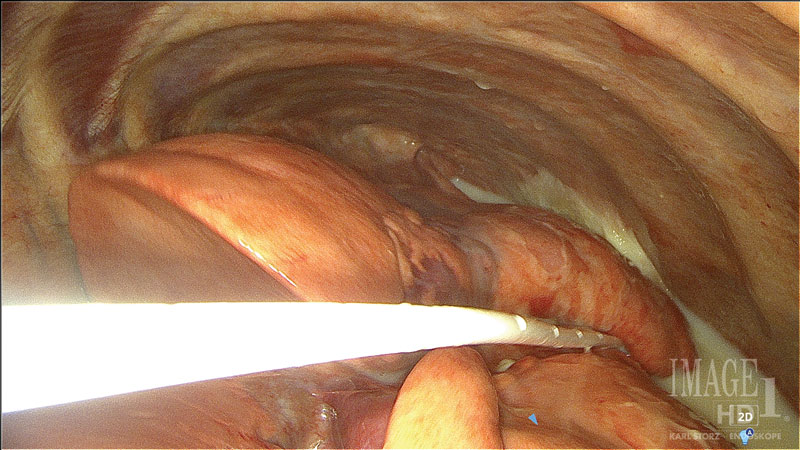

Surgical outcome for chylothorax in small animal patients is highly variable, with the prognosis more guarded in cats than in dogs.1,13 Traditional surgical interventions for idiopathic chylothorax are highly invasive, typically requiring open chest surgery (Figures 1 and 2) with the possibility of added abdominal laparotomy.3,4 Owners may be averse to such highly invasive procedures, with a possibility of nonresolution or continued need for pleural effusion evacuation. The use of minimally invasive surgery in small animals has made advances in the last several decades, and its use has been applied for surgical conditions, such as chylothorax.13-15

Figure 1. Thoracic duct ligation in a cat using the traditional intercostal thoracotomy approach. Photo courtesy Dr. Eric Monnet.